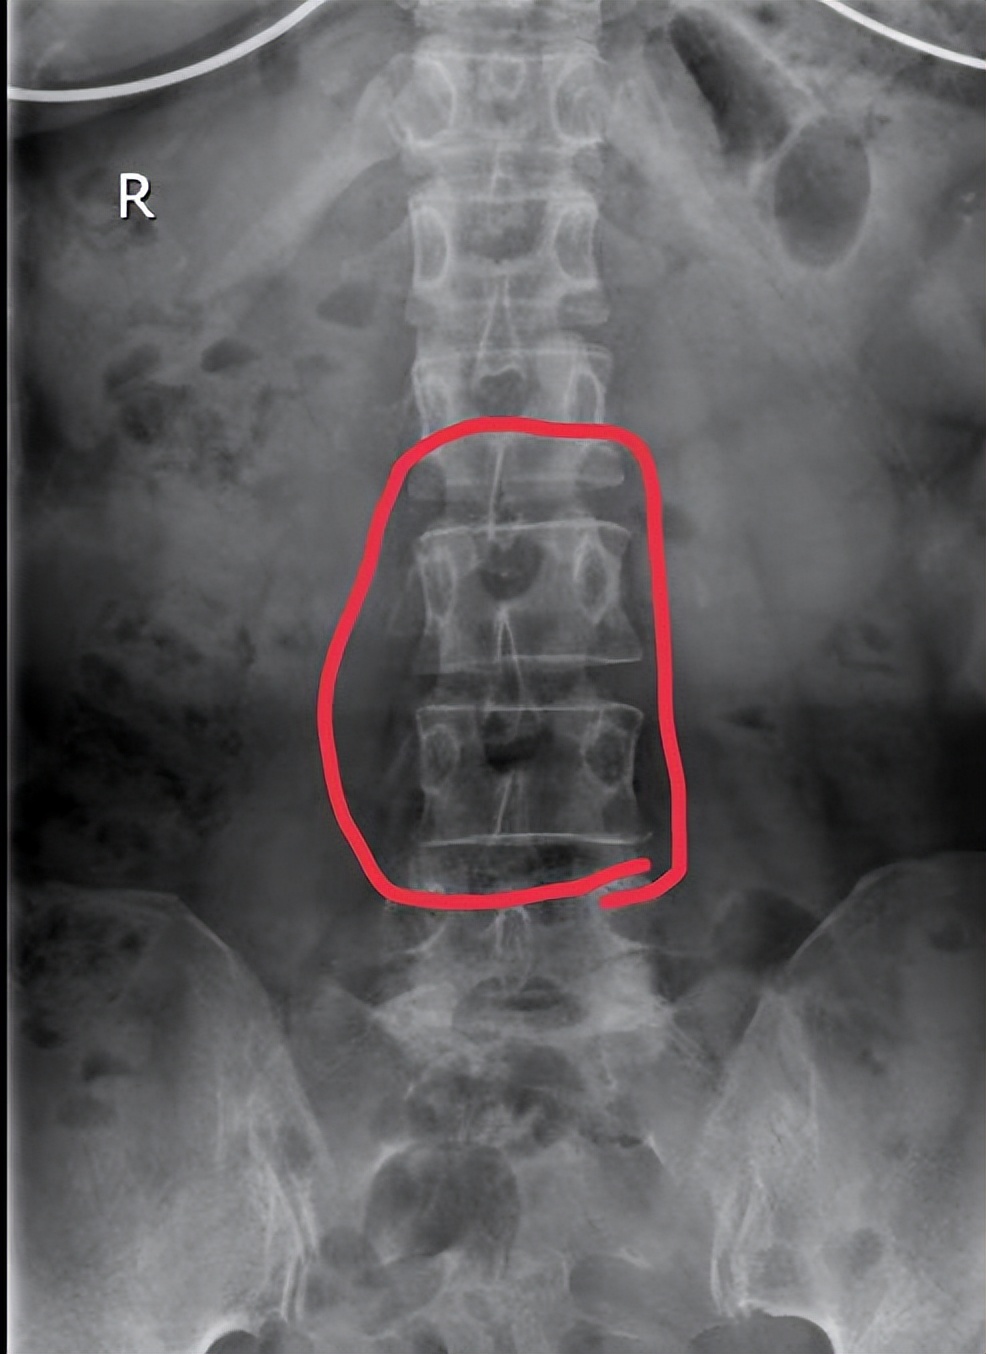

腰椎椎体右旋

在王美女接受治疗的几天内,接连接诊了数例此类患者,凡急性损伤患者,基本一次而愈,但反复腰椎关节紊乱发作,又没有得到有效治疗的患者,治疗周期就要长些。对于此类患者,则需要结合影像资料,确定罹患椎体及旋转方向,行针灸、针刀松解后,再行整脊复位,则可以收到较持久、较稳固的治疗效果。疫情期间承担志愿者工作的孙大姐,素有慢性腰痛病史,抬重物时又不慎扭伤腰部,腰臀及下肢麻痛持续不缓解来诊,经过上述治疗手段10余天的治疗,症状才得以缓解。孙大姐的腰痛,就是因为既往的腰椎错位没有得到及时有效纠正,在此基础上,又发生了新的损伤,缓解椎周肌肉的痉挛,纠正旋转错位的椎体及小关节,孙大姐的腰痛慢慢的就得到了缓解。